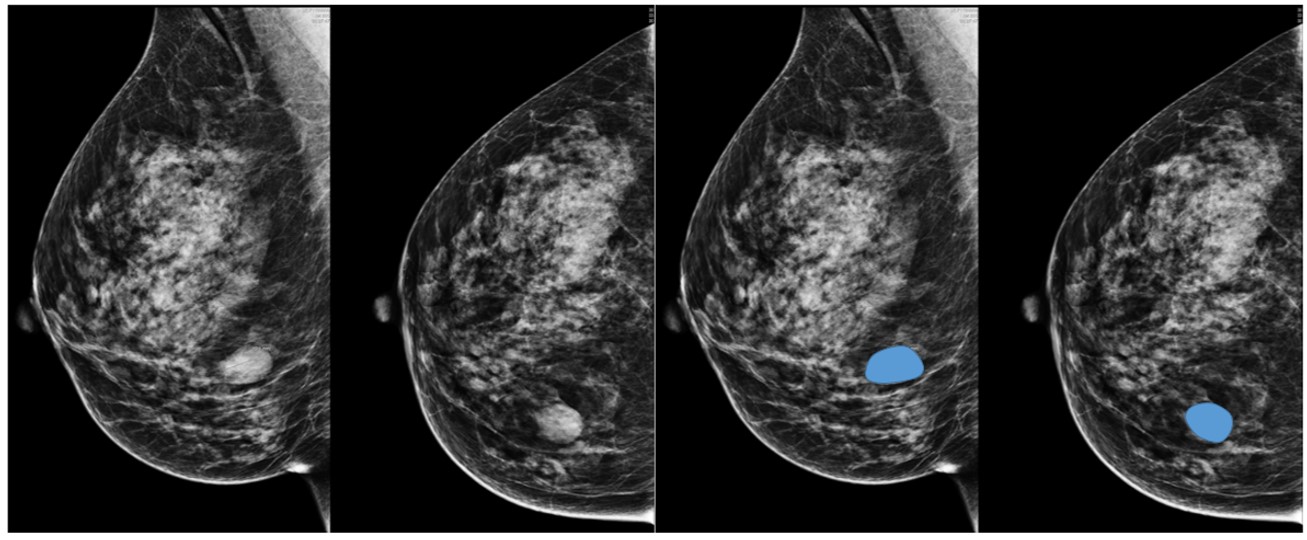

A neoplasia de mama e do colo de útero podem ser detectadas precocemente por meio da mamografia e da citologia oncótica respectivamente, exames não invasivos, de fácil aplicabilidade e baixo custo, compatíveis para o rastreamento em massa em uma população assintomática.